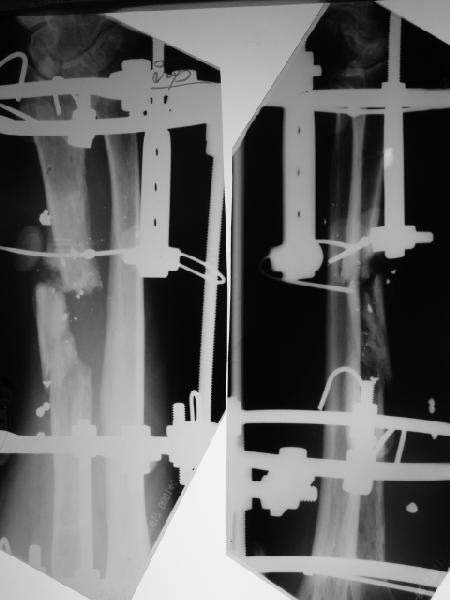

Alexander Chelnokov 22 Март 2004, 19:45

2

В приложении - снимок по окончании дистракции, и после смены аппарата на стержень (довольно толстый, 5 мм). С входом в канал на центральном отломке пришлось малость попотеть, промежуточный отломок его прикрывал. Но все-таки удалось закрыто проколупать. Надеюсь, дня через 3-4 после операции можно будет передать пациента нейрохирургам. Буду признателен за критику и комментарии.

Все за и про интрамедуллярной фиксации этого перелома луча уже обсуждались - все идет по плану.

Твоя концепция стабилизации отломков, своего рода *протезирования* лучевой кости продемонстрирована на Ргграммах. Прямого кость-кость контакта между дистальным и промежуточным фрагментами не получилось, что может скомпрометировать сращение перелома, хотя при первично стабильной фиксации и сохраненной надкостнице можно рассчитывать не

формирование периостальной мозоли (видимо этот механизм и работал в твоих прежних случаях).

Осталось дело за нейрохирургами и физиотерапевтами.